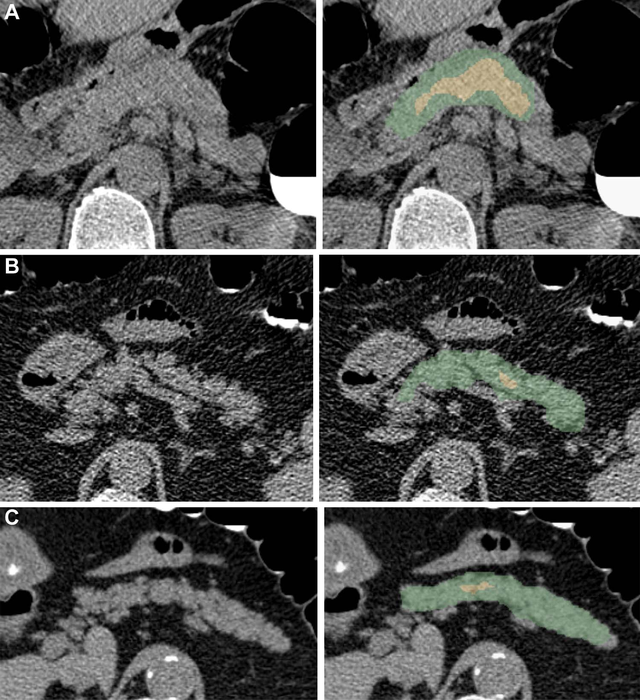

Abdominal CT imaging can be a promising tool to diagnose type 2 diabetes. CT imaging is already widely used in clinical practices, and it can provide a significant amount of information about the pancreas. Previous studies have shown that patients with diabetes tend to accumulate more visceral fat and fat within the pancreas than non-diabetic patients. However, not much work has been done to study the liver, muscles and blood vessels around the pancreas, said study co-senior author Ronald M. Summers, M.D., Ph.D., senior investigator and staff radiologist at the National Institutes of Health Clinical Center in Bethesda, Maryland.

The manual analysis of low-dose non-contrast pancreatic CT images by a radiologist or trained specialist is a time-intensive and difficult process. To address these clinical challenges, there is a need for the improvement of automated image analysis of the pancreas, the authors said.

The deep learning model displayed excellent results, demonstrating virtually no difference compared to manual analysis. In addition to the various pancreatic features, the model also analyzed the visceral fat, density and volumes of the surrounding abdominal muscles and organs.

The best predictors of type 2 diabetes in the final model included intrapancreatic fat percentage, pancreas fractal dimension, plaque severity between the L1-L4 vertebra level, average liver CT attenuation, and BMI. The deep learning model used these predictors to accurately discern patients with and without diabetes.